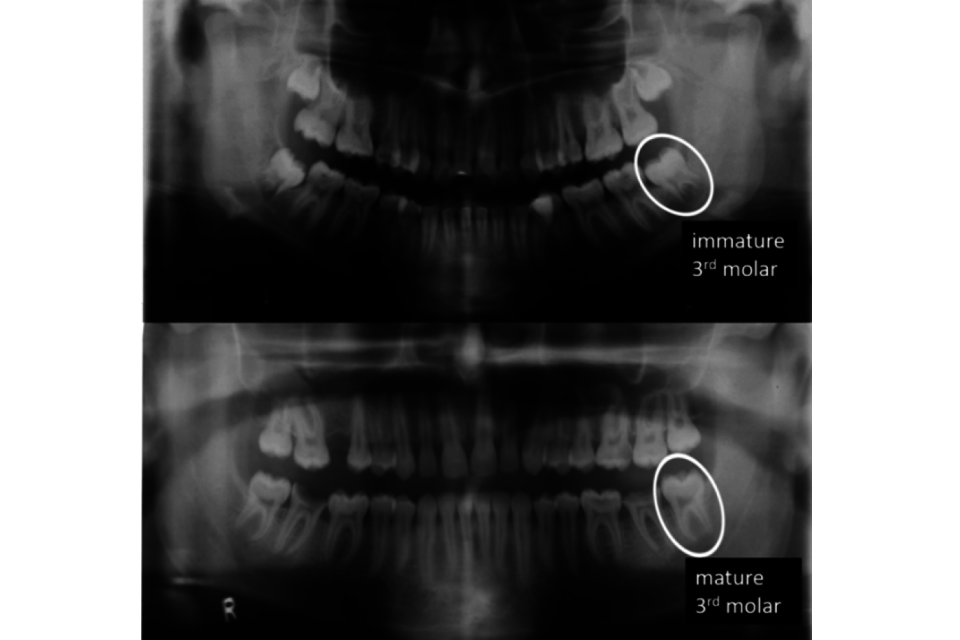

4.34. Maturity of the third molar is illustrated by Demirjian stage H when the apical end of the root canal is completely closed and the periodontal membrane has a uniform width around the root and the root apex (Demirjian et al., 1973) – see Figure 2.

Figure 2: Two orthopantomograms with the individual’s left mandibular third molar circled. The upper image, taken from a female aged 13, shows an immature third molar with roots not fully developed. The lower image, taken from a male aged 18, shows a mature third molar where root growth has ceased (Demirjian stage H).

Orthopantomograms as described above.